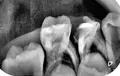

Ребенку 6 лет. Жаловалась на зубную боль, пришли к врачу. После осмотра, и рентгена врач сказала, что лечение не поможет. Но желательно не удалять как можно дольше потому, что воспаление корня далеко от коренного зуба. А если удалить, то зубы могут сместиться. Зуб не беспокоит больше недели уже. Но боюсь, что начнет болеть снова. На снимке этот зуб снизу слева (третий).